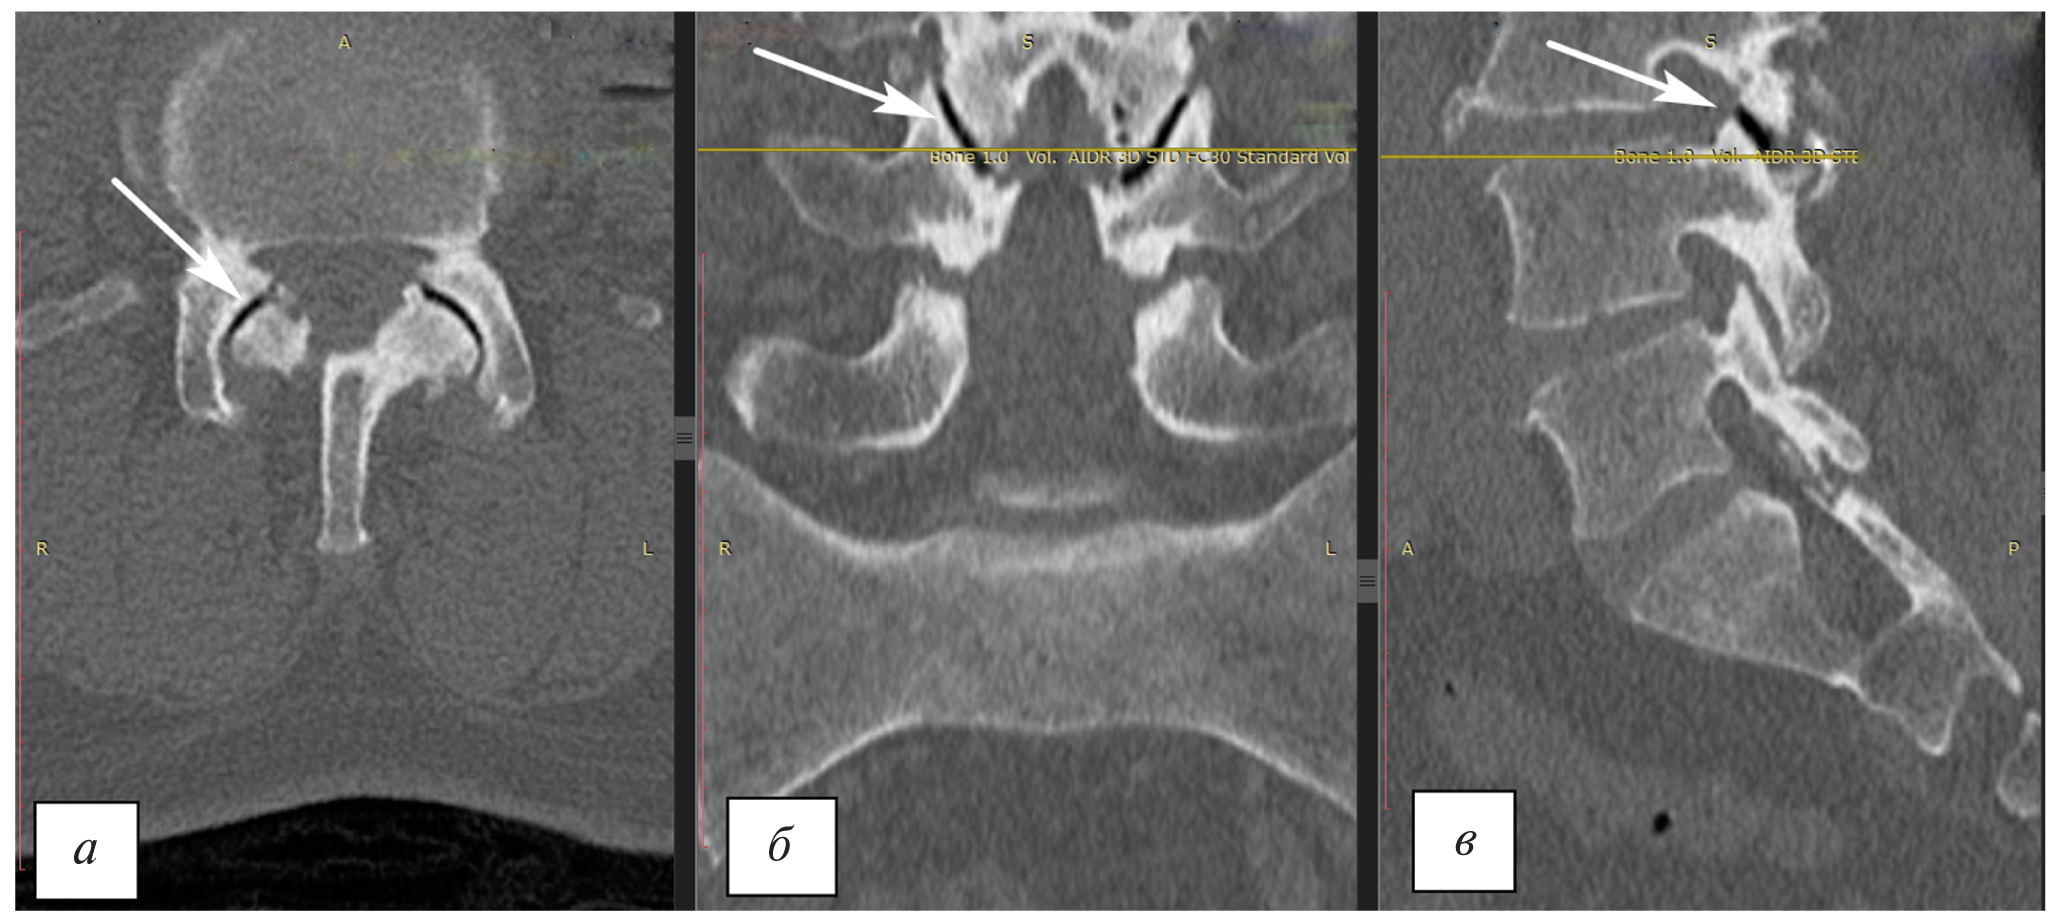

Исследование поясничного отдела позвоночника методом магнитно-резонансной томографии (МРТ) не выявило компрессии невральных структур позвоночного канала и признаков фораминального стеноза (рис. 1). Определяются дегенеративно-дистрофические изменения в дугоотростчатых суставах: суставные щели неравномерной ширины, замыкательные пластинки неровные, склерозировны. Спондилоартроз больше выражен справа на уровне LIII–LIV.

Рис. 1. Магнитно-резонансная томография поясничного отдела позвоночника: а — Т1-взвешенное изображение в сагиттальной проекции (гипоинтенсивный сигнал суставной щели гипертрофированных дугоотростчатых суставов LIII–LIV, стрелка); б — Т2-взвешенное изображение во фронтальной проекции (гипоинтенсивный сигнал суставной щели гипертрофированных дугоотростчатых суставов LIII–LIV, стрелка); в — Т1-взвешенное изображение в аксиальной проекции (гипоинтенсивный сигнал суставной щели гипертрофированных дугоотростчатых суставов LIII–LIV, стрелка). Тяжесть дегенеративных изменений в зигапофизарном суставе LIII–LIV справа соответствует IV степени по классификации A. Fujiwara. / Fig. 1. Magnetic resonance imaging of the lumbar spine: а — a T1-weighted image in the sagittal projection (a hypointensive signal of the articular gap of hypertrophied LIII–LIV arch-process joints, arrow); б — a T2-weighted image in the frontal projection (a hypointensive signal of the articular gap of the hypertrophied LIII–LIV arch–process joints, arrow); в — a T1-weighted image in the axial projection (hypointensive signal of the articular gap of the hypertrophied LIII–LIV arch-process joints, arrow). The severity of degenerative changes in the zygapophyseal LIII–LIV joint on the right corresponds to the IV degree according to A. Fujiwara’s classification.